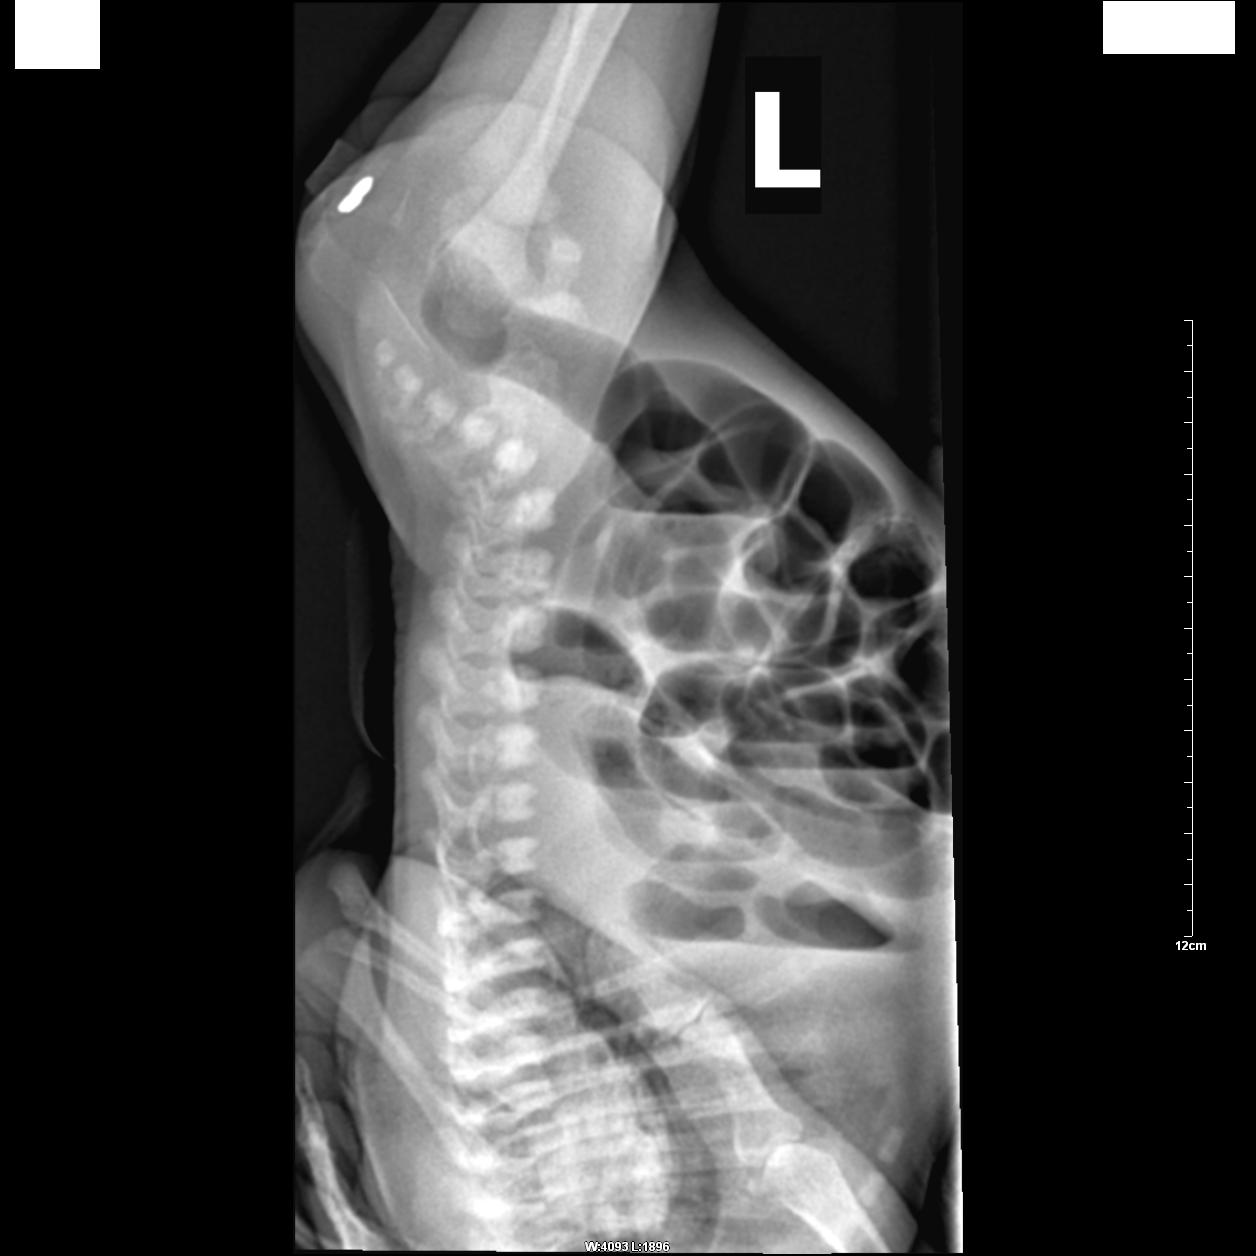

标题: PED0943:考虑先天性肛门闭锁。 [打印本页]

标题: PED0943:考虑先天性肛门闭锁。

患者,女,生后7天无排便。

肛门部位标记,腹部倒立正侧位:

典型!肌性闭锁。

看到26楼还是没有一个人去具体诊断,如果临床要你去诊断\"肌性闭锁\",那他们可以不拍片了.术前临床需要什么?这才是照片的目的,我们需要告诉临床,闭锁是高位还是低位,还是中位,那么具体到胶片上就是找pc线了.一味的同意,一味的支持,一味的典型,能给\"临床大夫一做直肠指诊不就得了\"\"做个直肠镜就可以\"回帖者什么好处?如果没人指点,他们永远在迷宫里.

相信大家都能明确诊断,希望回帖品质再提高点,让更多初学者在这里有更多收获.